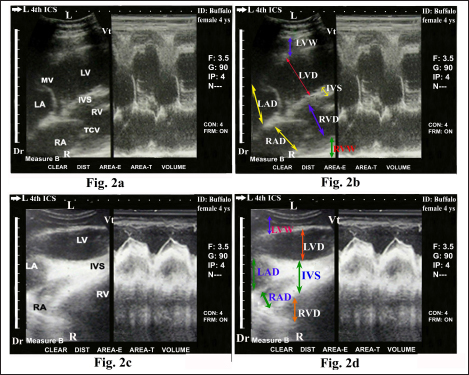

The heart was imaged from the left fourth ICS in midway between the elbow and shoulder points as the angle of the transducer directed dorsally and slightly cranially toward the third ICS, showing visualization of the right ventricular outflow tract (RVOT); RA, RV, TCV, PA, and pulmonary valve (PV) (Fig. 3). Cross sections at the apex of the heart, either in diastole (Fig. 4a) or systole status (Fig. 4b) showed RV and LV. Cross sections in the base of the heart showed RA, LA, TCV, and MV either in diastole (Fig. 5a) or systole status (Fig. 5b). Regular and strong myocardial contractility was clearly observed in both B-mode and m-mode 2-D-gray scale ultrasonography in all buffaloes.

Fig. 4. Echocardiogram of caudal long axis view in adult healthy female non-pregnant (5-year-old) buffalo (left side) during diastole (a) and systole (b) using a 3.5 MHz sector 2-D-gray scale transducer (B-mode and M-mode). It was imaged from the left fourth ICS in the midway between the elbow point and shoulder point. It showed CS in the apex of the healthy heart with regular, strong contractions and clear margins. The RV, LV, and IVS were clearly visualized. Dr; Dorsal. Vt; Ventral. R; Right. L; Left.